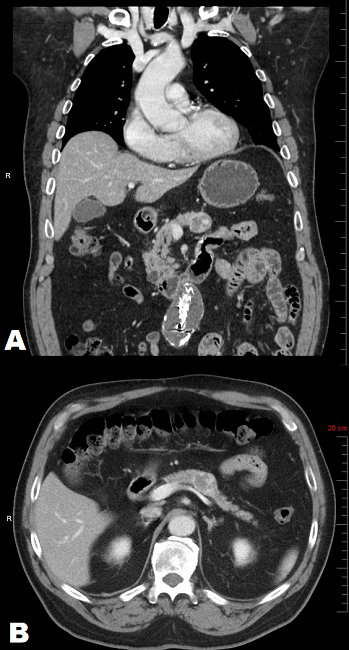

A 69-year old male with a past medical history of chronic hypercholesterolemia, hypertension and morbid obesity and remote history of alcohol and tobacco use was incidentally discovered to have a 2.5 cm partially calcified, cystic mass within the body of the pancreas. The mass was discovered as an incidental finding on CT angiogram of the abdomen (Figures 1A and 1B) during the evaluation for an abdominal aortic aneurysm. Follow-up esophagogastroduodenoscopy/endoscopic-ultrasound highlighted a 2.7 × 2.6 cm hypoechoic, heterogeneous, partially calcified lesion abutting the splenic vein (Figure 1).